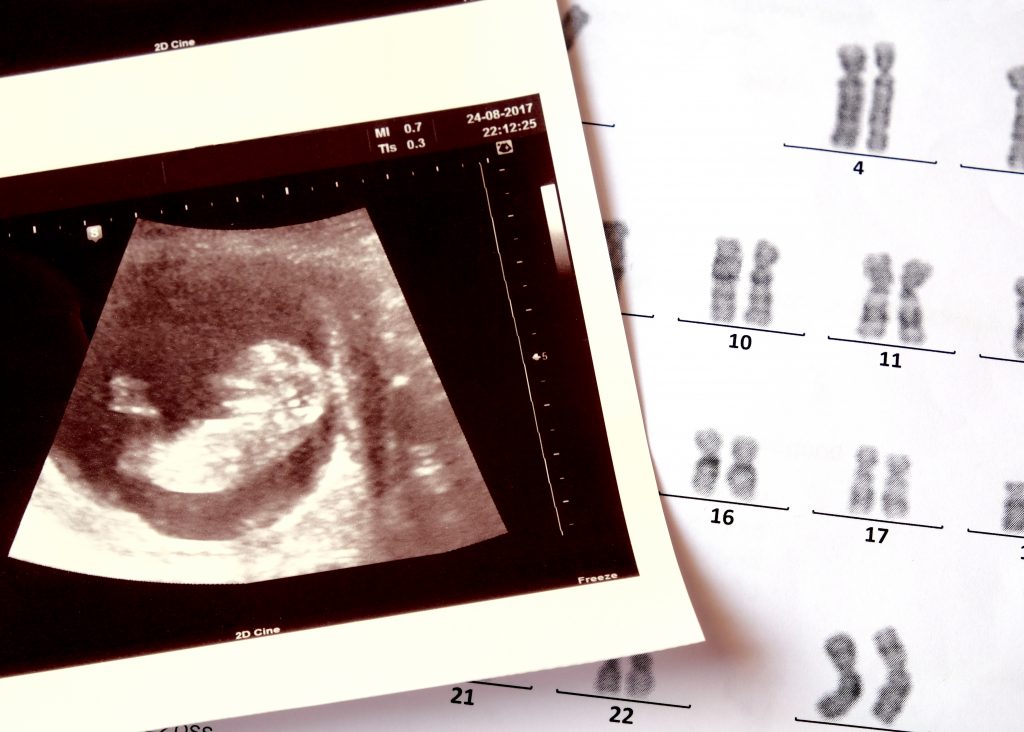

Пренаталдық генетикалық тесттер дегеніміз не?

Бұл болашақ ата-аналарға балаларында болуы мүмкін генетикалық бұзылыстар туралы ақпарат беруге арналған тестілер. Генетикалық аурулардың көпшілігі ата-аналардың біреуінен немесе екеуінен де тұқым қуалайды, сондықтан оларды жүктіліктің ерте мерзімінде анықталғаны дұрыс. Бұл жерде атап өту керек, Егер ата-аналар генетикалық тасымалдаушы емес екеніне көз жеткізгісі келсе,кейбір тесттерді жүктілік басталмай тұрып та жасауға болады.Қазіргі уақытта біз тек пренатальды мәселелерге ғана назар аударамыз.

Пренаталдық генетикалық тесттердің екі негізгі түрі бар. Пренаталдық скринингтік тесттер және пренаталдық диагностикалық тесттер. Пренаталды скринингтік тесттер – балада туа біткен ақау болуы мүмкін бе екенін анықтайды (ықтимал қауіп деңгейін көрсетеді). Пренаталды диагностикалық тесттер – нәрестеде нақты генетикалық ауру бар-жоғын дәл анықтайды. Диагностикалық тесттер – бұл нақты диагноз қоюдың жалғыз жолы.

Бірінші триместрде аралас скрининг деп аталатын бірінші триместрдегі скринингтік тестілер неғұрлым кең таралған болып табылады. Оларға Даун синдромының (21-трисомия немесе 21-қалыпта қосымша хромосоманың болуы), Эдвардс синдромының (18-трисомия) және Патау синдромының (13-трисомия) даму қаупін көрсететін тесттер жатуы мүмкін. Талдауларға қан талдаулары, желке астының мөлдірлігін ультрадыбыстық зерттеу (НЦ), ананың жасы мен салмағын, сондай-ақ жүктілік жасын анықтау кіреді. Әдетте оларды жүктіліктің 9-шы және 13-ші апталары аралығында жасайды.

Бұл тесттер дамушы баланың хромосомдық аномалиясы бар ма, жоқ па, 99,9% -дан астам дәлдікпен анықтай алады. Неғұрлым жиі пайдаланылатын амниоцентез болып табылады, ол екінші триместрде жүргізіледі. Әдетте, егер скринингтік тест бірінші триместрде генетикалық ауру қаупінің белгілі бір деңгейін көрсетсе немесе анасы 35 жастан асқан болса, дәрігер диагностикалық тестті ұсына алады.